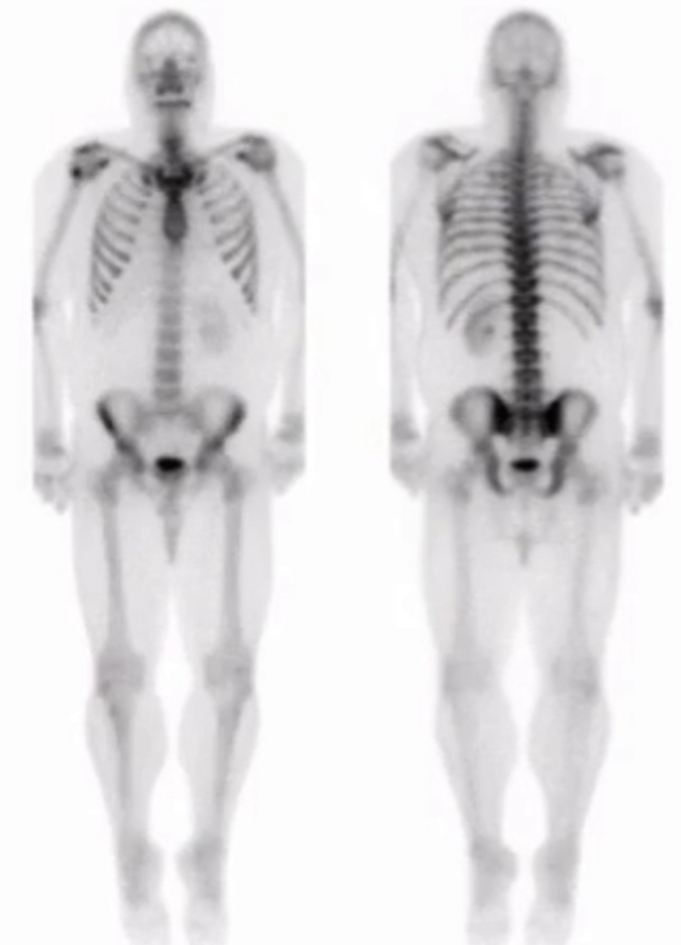

Superscan

• Diffuse uniform tracer uptake throughout the skeleton

• Will see concurrent decreased renal activity

• Most commonly due to prostate carcinoma

• Other things looking similar if no cancer —> hyperparathyroidism